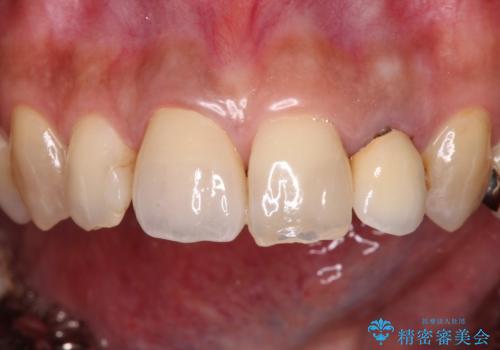

- 保険診療でのクラウンが変色してしまったとのことで来院された患者様です。

根管治療がされていなかったため、まずは根管治療を行い、その後オールセラミッククラウンにて補綴することとしました。

左上の歯も歯肉縁部分にメタルの色が見えており、合わせて治療することをお勧めしましたが、今回は1歯のみを治療することとしました。